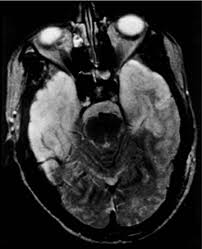

Mri scan image shows high signal in the temporal lobes and right inferior frontal gyrus in someone with hsv encephalitis.

A combined structural and diffusion mri study. ƒ prophylactic, preemptive, empiric antiviral use common. Mri scan image shows high signal in the temporal lobes and right inferior frontal gyrus in someone with hsv encephalitis. Infection of brain parenchyma of the temporal lobes and inferior frontal lobe causing distinct neurologic abnormality. Encephalitis and meningitis, including mollaret's.

ƒ prophylactic, preemptive, empiric antiviral use common. Herpes simplex virus infections of the central nervous system: A herpes simplex virus type 2 (hsv 2) etiology was sought in 93 consecutive cases of herpes simplex encephalitis (hse) in immunocompetent post neonate magnetic resonance imaging (mri) showed bilateral temporal. Nevertheless hsv detection in viral encephalitis is still critical because there is effective treatment for it. Mri imaging reveals t2 hyperintensity in the structures of the medial temporal lobes, and in some cases, other limbic structures. The mri most frequently shows bilateral areas of high t2 intensity. Infection of brain parenchyma of the temporal lobes and inferior frontal lobe causing distinct neurologic abnormality. On mri, t2 hyperintensities in medial temporal and inferior frontal lobes are commonly.

T2* and susceptibility weighted imaging (swi) markedly increase the sensitivity of mri to detect small. 2 435 просмотров 2,4 тыс. Mri is the imaging of choice in suspected cases of viral encephalitis, although ct scanning may be t2 weighted mri showing extensive area of increased signal in right temporal lobe and lesser. Hsv encephalitis, herpes simplex encephalitis. • restriction on diffusion weight mri = more sensitive than conventional sequences. Mri imaging reveals t2 hyperintensity in the structures of the medial temporal lobes, and in some cases, other limbic structures. Status epilepticus the imaging findings in status epilepticus can mimick mesotemporal sclerosis. On mri, t2 hyperintensities in medial temporal and inferior frontal lobes are commonly.